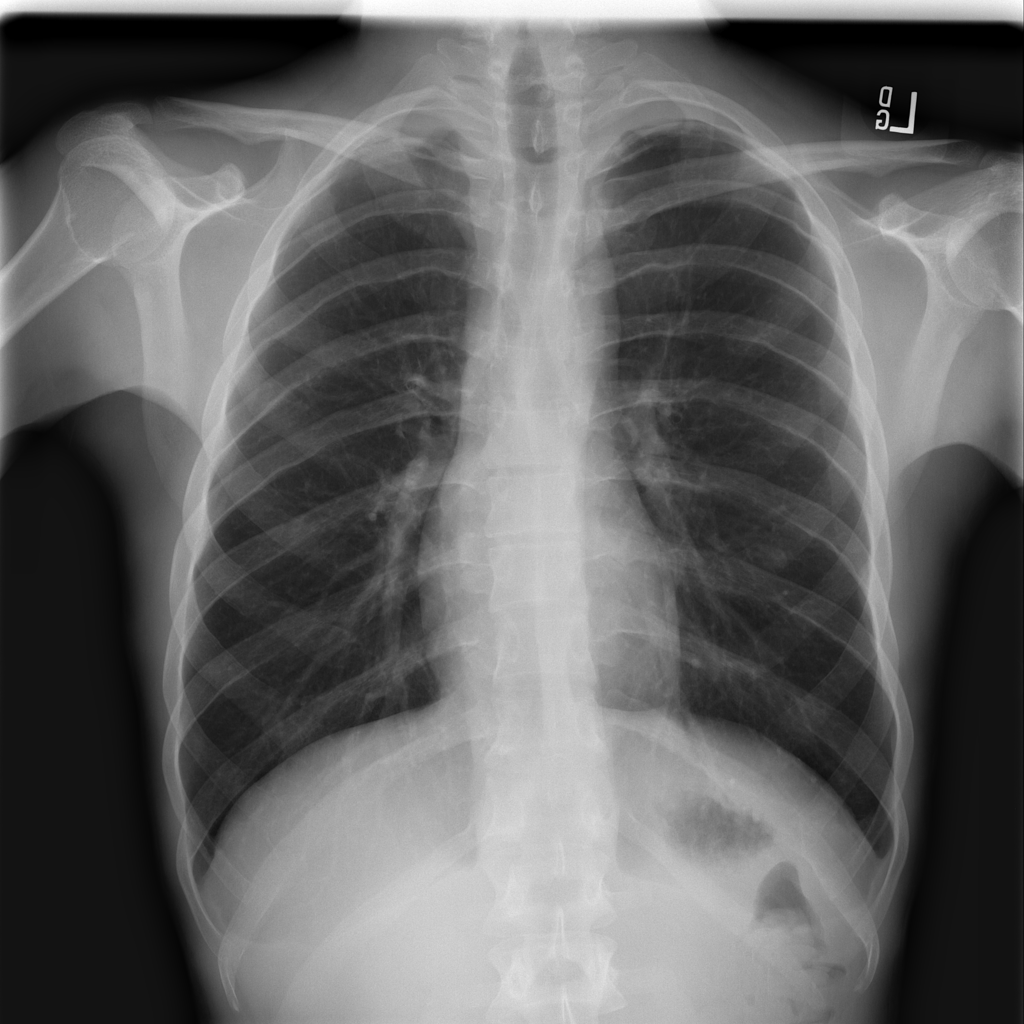

Mass

A mass is a larger focal opacity or lesion seen on the image. It is a descriptive finding that can have several causes and usually needs more imaging or clinical context to characterize.

PAT-C0E5 · IMG-001Mass

PAT-C0E5 · IMG-001

PA